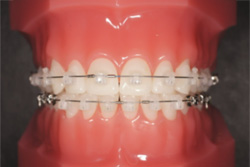

¡Ú¾ÉÎã1¡Û¥Þ¥ë¥Á¥Ö¥é¥±¥Ã¥ÈË¡¤Ç¼£ÎŤò¹Ô¤Ã¤¿À®¿Í¶ºÀµ¤Î¾ÉÎã

- ¼£ÎÅÁ°

- ¼£ÎÅÃæ

- ¼£ÎŸå

- ¥Þ¥ë¥Á¥Ö¥é¥±¥Ã¥ÈË¡¤Ç¼£ÎŤò¹Ô¤Ã¤¿À®¿Í¶ºÀµ¤Î¾ÉÎã

´µ¼ÔÍͤξɾõ

Angle Iµé¡¢±±»õ¤Î³ú¤ß¹ç¤ï¤»¤ËÁ°¸åÊý¸þ¡¢Æâ³°¤ÎÊý¸þ¤Î³ú¤ß¹ç¤ï¤»¤Î¤º¤ì¤Ïǧ¤á¤Þ¤»¤ó¤Ç¤·¤¿¤¬¡¢Á°»õ¤Î¥¹¥Ú¡¼¥¹ÉÔÂ(Í𹺻õ)¤È±¦Â¦¤Î¦ÀÚ»õ¤Î¸òºµÒû¹ç(ËÜÍè¡¢¾å¤Î»õ¤¬³°Â¦¡¢²¼¤Î»õ¤¬Æâ¦¤Ë¤¢¤ë¤â¤Î¤¬¡¢µÕ¤Ë¤Ê¤Ã¤Æ¤¤¤ë¾õÂÖ)¤òǧ¤á¤Þ¤·¤¿¡£

¤Þ¤¿¡¢¾å¤Î¦ÀÚ»õ¤Ïâä¾®»õ¤È¤Ê¤Ã¤Æ¤¤¤Þ¤·¤¿¡£ -

¼£ÎÅË¡

¾å¤Î¦ÀÚ»õ¤¬âä¾®»õ¤Ç¡¢¥µ¥¤¥º¤¬¾®¤µ¤¤¤¿¤á¡¢¾å²¼¤ÎÁ°»õ¤Î¥µ¥¤¥º¥Ð¥é¥ó¥¹¤¬°¤¤¾õÂ֤Ǥ·¤¿¡£

¤½¤Î¤¿¤á¡¢º¸²¼¤ÎÁ°»õ1ËܤòÈ´»õ¤·¤Æ¡¢¥µ¥¤¥º¥Ð¥é¥ó¥¹¤òÀ°¤¨¤ë¤È¤È¤â¤Ë¡¢»õÊÂ¤Ó¤ÎÆÌ±ú¤ò¤Û¤°¤¹¤¿¤á¤Î¥¹¥Ú¡¼¥¹¤È¤·¤ÆÍøÍѤ·¤Þ¤·¤¿¡£

¥Þ¥ë¥Á¥Ö¥é¥±¥Ã¥ÈÁõÃÖ¤òÁõÃ夷¡¢ÇÓÎó¤ò¹Ô¤¤¤Þ¤·¤¿¡£ -

¼£ÎÅ·ë²Ì

¸òºµÒû¹ç¡¢ÁÑÀ¸¤Ï²þÁ±¤·¡¢¤¤ì¤¤¤ËÇÓÎ󤵤ì¤Þ¤·¤¿¡£